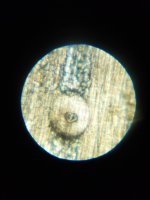

Не секрет) Паразитарку рыбы, например. Я трихинеллез смотрела после обнаружения на Стейкере. Делала фото для наглядных пособий для ветакадемии в Питере яиц и личинок дифиллоботриоза, описторхоза, трихинеллеза. Студенты, молодые врачи приходят, а у нас целая подборка всякой пакости. Сейчас уже расширили перечень исследований. Если на Бимаме трихинелла в таком виде, на той бандуре она во всей красе. 1764179005506.jpg